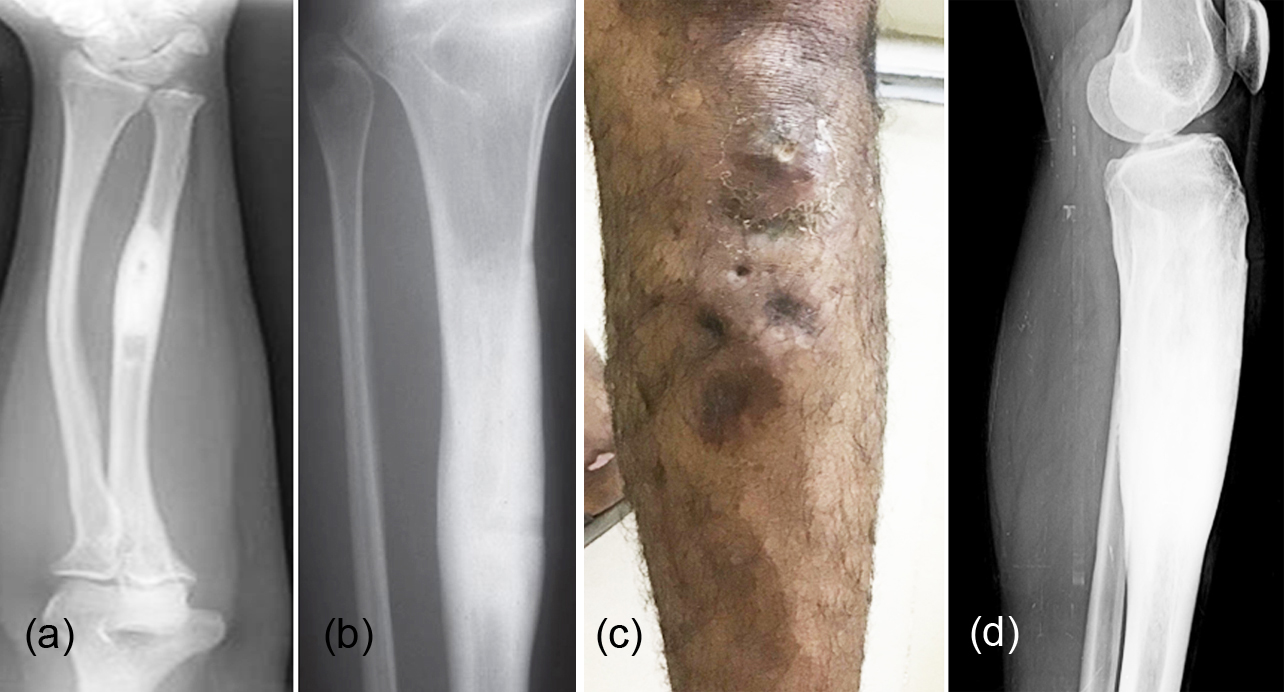

İdiyopatik Periostit (Garre Osteomyeliti) teşhisi, genellikle klinik muayene ve görüntüleme teknikleriyle konulur. Doktorlar, öncelikle çocuğun tıbbi geçmişini detaylı bir şekilde değerlendirir ve belirtileri analiz eder. Ardından, röntgen, manyetik rezonans görüntüleme (MR) veya bilgisayarlı tomografi (BT) gibi yöntemler kullanılarak kemik yapısı incelenir. Bu görüntüleme teknikleri, kemik çevresindeki iltihaplanmayı ve kemik dokusundaki değişiklikleri tespit etmek için oldukça etkilidir.

Bazı durumlarda, enfeksiyon olasılığını dışlamak için kan testleri veya biyopsi gibi ek yöntemlere başvurulabilir. Kemik iltihabı ile karışabilen bu tablonun doğru bir şekilde ayırt edilmesi, tedavi sürecinin başarısı için kritik bir öneme sahiptir. Uzman bir doktorun yönlendirmesiyle, teşhis süreci hızlı ve güvenilir bir şekilde tamamlanabilir.